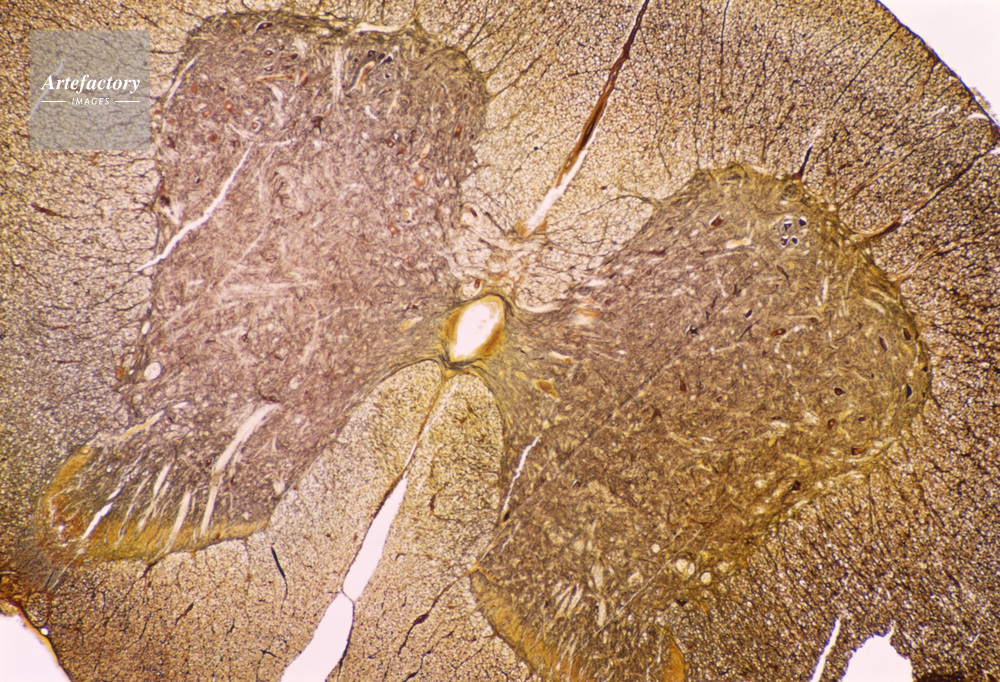

| 作品番号 | 06400173 | クレジット表記 | (c)JAPACK / Artefactory | |

| 作品タイトル | 顕微鏡写真 | モデルリリース | なし | |

| キャプション | 脊髄,猫,20倍 | 制限事項 | ||

| ソース | ピクセル数 | 5546px × 3783px | ||

| 撮影地 | 印刷サイズ | 30.2cm × 20.6cm | ||